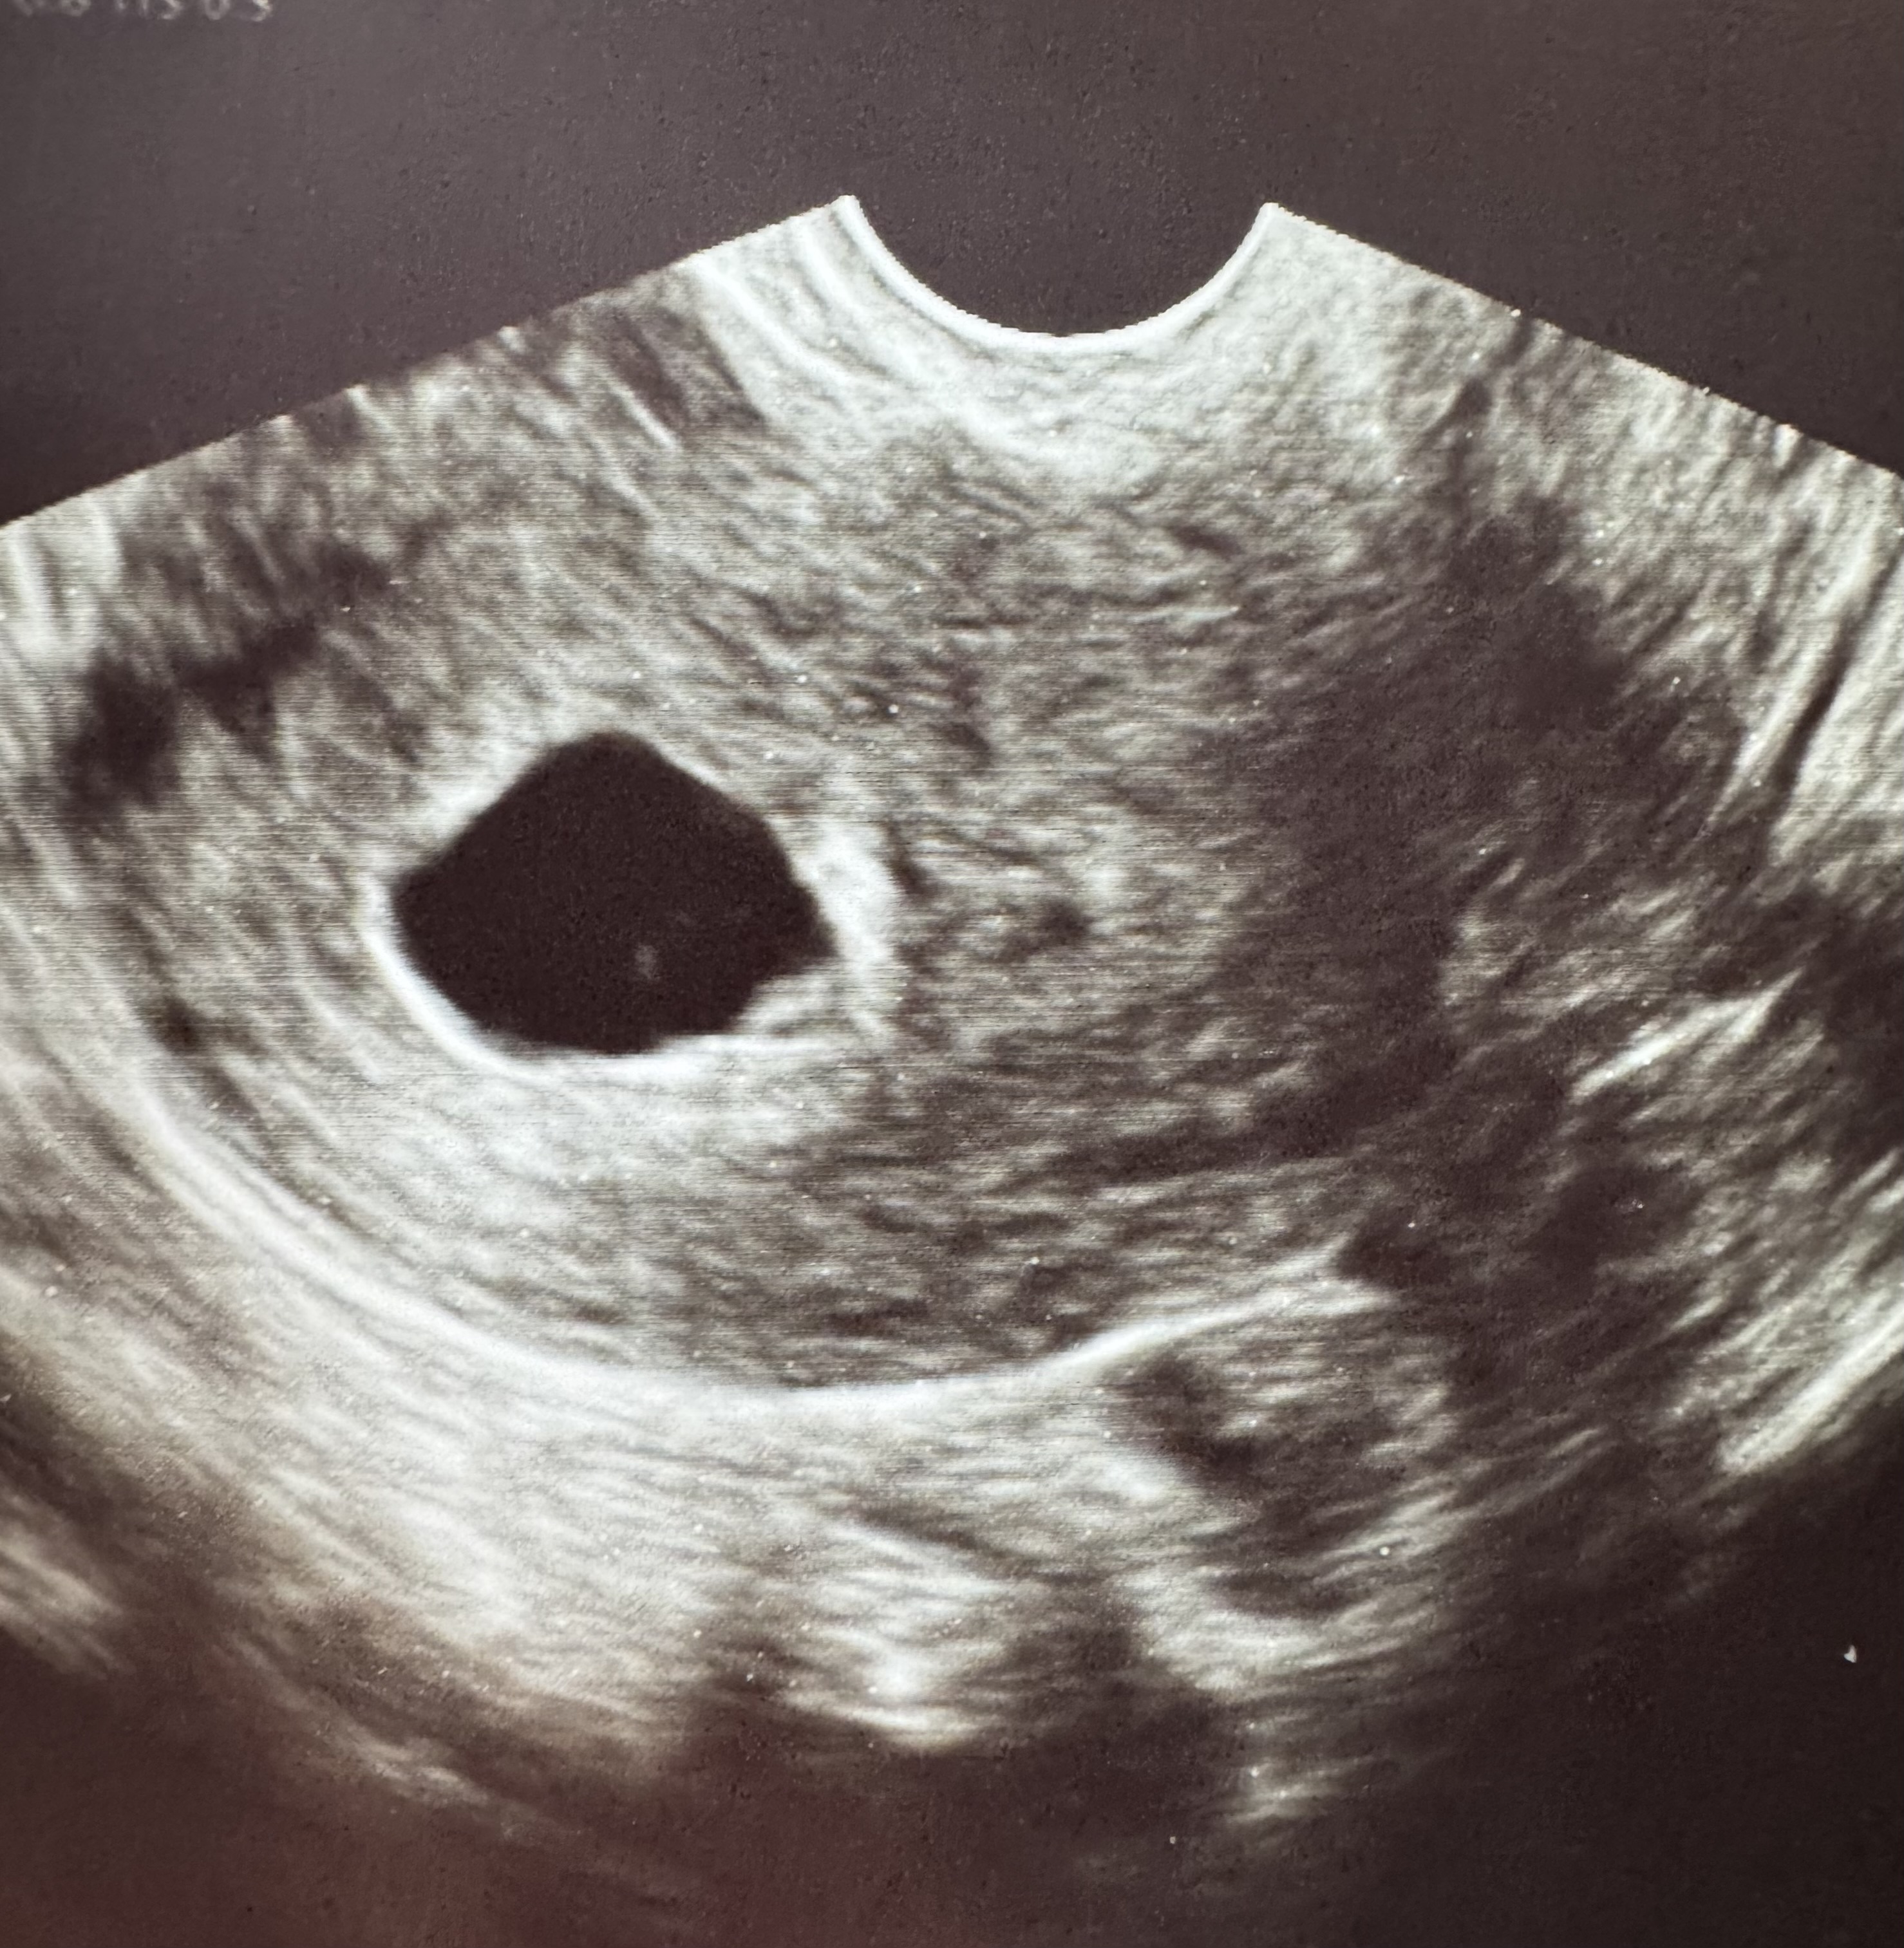

29 ДПП или ровно 7 недель 🌸

Ре говорит «Не дыши так глубоко, я датчиком поймать ничего не могу» 😅Я повернула голову, а Ре мне его сразу показала, маленькую креветочку

Сердцебиение увидела отчетливо в этот раз. Послушать увы не смогли, датчик ничего не поймал из-за того что малышок не очень удачное место выбрал, чтобы датчик его подцепил.🥲 Но визуально Ре сказала отличное ритмичное сердцебиение. Маленькая победа 🤞 Контрольное узи так же 8 марта, надеюсь я доживу до субботы 😅